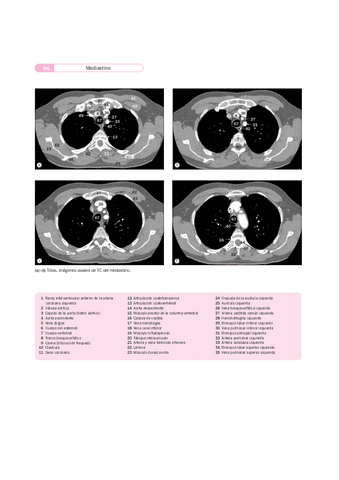

Apuntes - Imágenes radiológicas TAC RM.pdf